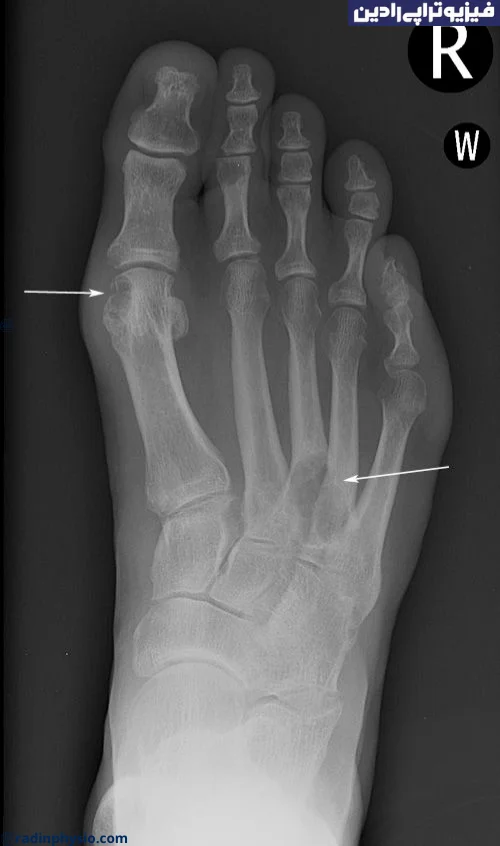

برای تشخیص و درمان آرتروز اولیه، بهتر است به پزشک متخصص ارتوپدی مراجعه کنید. پزشک با انجام بررسیهای فیزیکی، مشاهده علائم، و در صورت لزوم انجام تستهای تصویری مانند ایکسری یا سونوگرافی، تشخیص صحیح داده خواهد شد و برنامه درمانی مناسب را تعیین خواهد کرد.

مهم است که در صورت تجربه هر یک از این علائم و نشانهها، به پزشک مراجعه کنید تا تشخیص دقیق و درمان مناسب را دریافت کنید. پزشک معالج شما ممکن است با توجه به علائم، انجام آزمایشات تشخیصی مانند رادیوگرافی (X-ray) و ارزیابی بالینی، به تشخیص دقیقتر برسد. همچنین، درمان آرتروز معمولاً شامل ترکیبی از تغییرات در سبک زندگی، فیزیوتراپی، داروها و در صورت لزوم، جراحی نیز میشود.